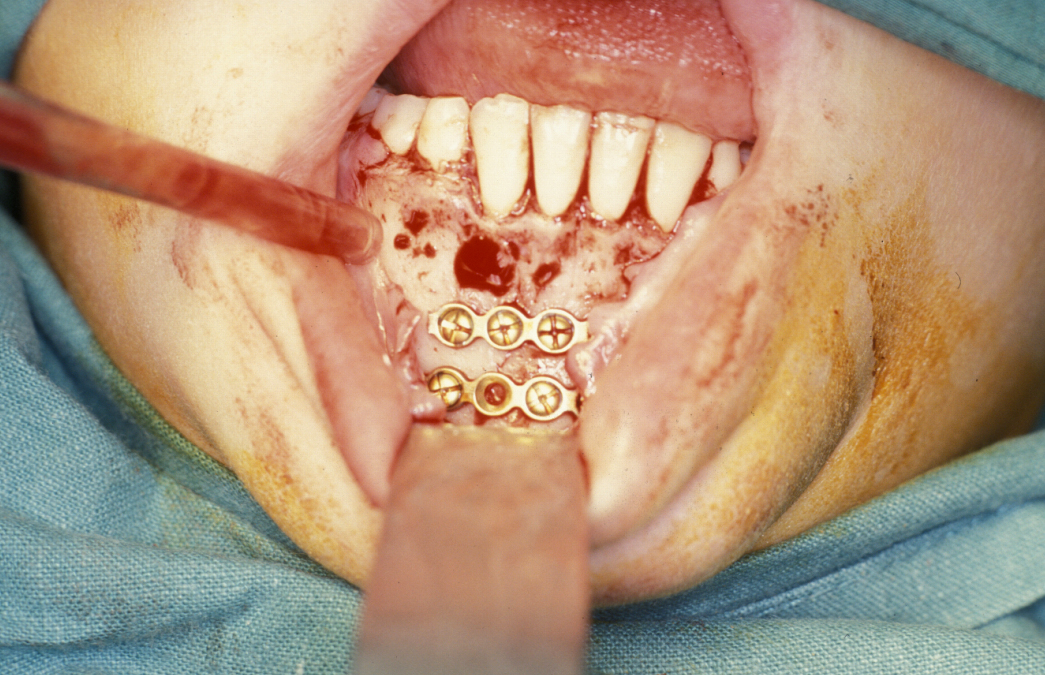

Fixation is undertaken with titanium mandibular plates. According to Champy’s principles, in the mandibular symphyseal and parasymphyseal (the middle region of the mandible) region two mandibular plates are required, one just below the level of incisor/premolar apices and above the mental foramen and one as low down on the buccal surface as possible parallel to the lower border of the mandible. This is shown in Figure 4.

In the region of the angle of the mandible, a single plate is adequate to allow healing. In practice many surgeons now supplement this (or even replace it) with a transbuccally placed lateral plate which prevents lateral displacement of the lower border of the mandible. All these techniques use monocortically placed matching titanium screws to retain the plates which immobilise the fracture sites. Long-acting local anaesthetic regional block provides good postoperative analgesia and prophylactic broad-spectrum antibiotics are given preoperatively. Intraoral wounds are closed with resorbable sutures. If the occlusion is fully restored and stability of the fracture is assured by the plates, the intermaxillary fixation can be removed. Postoperative radiographs are taken to ensure correct placement of plates and screws and accurate realignment of mandibular fragments. It is also important to reassess the position of the condyles following ORIF as malpositioning can lead to TMJ problems later on (see Figure 5).